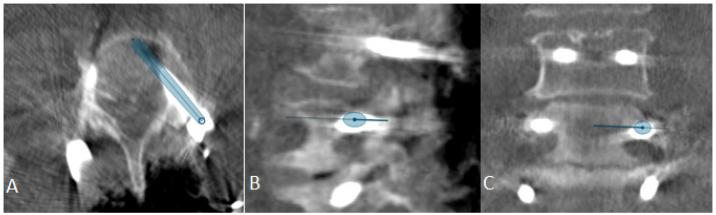

The aim of this study is to present the initiation of robotic-guided (RG) spine surgery into routine clinical care at a single center with the use of intraoperative CT (iCT) automatic registration-based navigation. The workflow included iCT with automatic registration, fusion with preoperative imaging, verification of preplanned screw trajectories, RG introduction of K-wires, and the insertion of pedicle screws (PSs), followed by a control iCT scan. All patients who underwent RG implantation of pedicle screws using the Cirq robotic arm (BrainLab, Munich, Germany) in the thoracolumbar spine at our department were included in the study. The accuracy of the pedicles screws was assessed using the Gertzbein-Robbins scale (GRS). In total, 108 patients (60 female, mean age 68.7 ± 11.4 years) in 109 surgeries underwent RG PS placement. Indications included degenerative spinal disorders ( = 30 patients), spondylodiscitis ( = 24), tumor ( = 33), and fracture ( = 22), with a mean follow-up period of 7.7 ± 9 months. Thirty-seven cases (33.9%) were performed percutaneously, and all others were performed openly. Thirty-three operations were performed on the thoracic spine, forty-four on the lumbar and lumbosacral spine, thirty on the thoracolumbar, one on the cervicothoracic spine, and one on the thoracolumbosacral spine. The screws were inserted using a fluoroscopic (first 12 operations) or navigated technique (latter operations). The mean operation time was 228.8 ± 106 min, and the mean robotic time was 31.5 ± 18.4 min. The mean time per K-wire was 5.35 ± 3.98 min. The operation time was lower in the percutaneous group, while the robot time did not differ between the two groups. Robot time and the time per K-wire improved over time. Out of 688 screws, 592 were GRS A screws (86.1%), 54 B (7.8%), 22 C (3.2%), 12 D (1.7%), and 8 E (1.2%). Seven screws were revised intraoperatively, and after revision, all were GRS A. E screws were either revised or removed. In the case of D screws, screws located at the end of the construct were revised, while so-called in-out-in screws in the middle of the construct were not revised. Brainlab's Cirq Robotic Alignment Module feature enables placement of pedicle screws in the thoracolumbar spine with high accuracy. A learning curve is shown through improvements in robotic time and time per K-wire.

本研究的目的是介绍在单一中心将机器人引导(RG)脊柱手术引入常规临床护理,采用术中CT(iCT)基于自动配准的导航技术。工作流程包括iCT自动配准、与术前影像融合、预规划螺钉轨迹验证、RG引导下克氏针置入以及椎弓根螺钉(PS)植入,随后进行对照iCT扫描。本研究纳入了在我们科室接受使用Cirq机器人手臂(德国慕尼黑BrainLab公司)在胸腰椎进行RG椎弓根螺钉植入的所有患者。使用Gertzbein-Robbins量表(GRS)评估椎弓根螺钉的准确性。总共109例手术中的108例患者(60例女性,平均年龄68.7±11.4岁)接受了RG PS置入。适应证包括退行性脊柱疾病(n = 30例患者)、脊椎间盘炎(n = 24)、肿瘤(n = 33)和骨折(n = 22),平均随访期为7.7±9个月。37例(33.9%)为经皮手术,其余均为开放手术。胸椎手术33例,腰椎和腰骶椎手术44例,胸腰椎手术30例,颈胸椎手术1例,胸腰段手术1例。螺钉采用透视技术(前12例手术)或导航技术(后序手术)置入。平均手术时间为2(28.8±106)分钟,平均机器人操作时间为31.5±18.4分钟。每根克氏针的平均时间为5.35±3.98分钟。经皮组的手术时间较短,而两组的机器人操作时间无差异。机器人操作时间和每根克氏针的时间随时间有所改善。在688枚螺钉中,592枚为GRS A级螺钉(86.1%),54枚为B级(7.8%),22枚为C级(3.2%),12枚为D级(1.7%),8枚为E级(1.2%)。7枚螺钉在术中进行了翻修,翻修后均为GRS A级。E级螺钉要么进行了翻修,要么被取出。对于D级螺钉,位于结构末端的螺钉进行了翻修,而结构中间的所谓进出式螺钉未进行翻修。Brainlab公司的Cirq机器人对准模块功能能够高精度地在胸腰椎置入椎弓根螺钉。通过机器人操作时间和每根克氏针时间的改善显示出学习曲线。